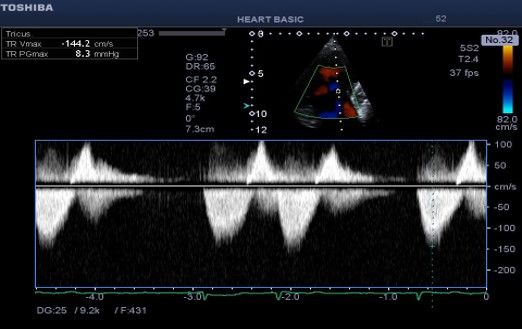

Εικόνα 2 . Συνεχές Doppler δια της τριγλώχινας . Το σχήμα του σήματος της

τριγλωχινικής ανεπάρκειας είναι τριγωνικό λόγω εξίσωσης πιέσεων μεταξύ δεξιάς κοιλίας και δεξιού κόλπου και θυμίζει αορτική ροή (αορτοποίηση).

Υπάρχει βραχεία άνοδος της ταχύτητας ροής (επηρεασμένο dp /

ενδεικτικό συστολικής δυσλειτουργίας της δεξιάς κοιλίας. Η προς τα

πρόσω ροή (κύμα Ε) της τριγλώχινας έχει σχετικά υψηλή ταχύτητα παρά τη

διάταση του δακτυλίου εύρημα σχετιζόμενο με την αυξημένη ροή.